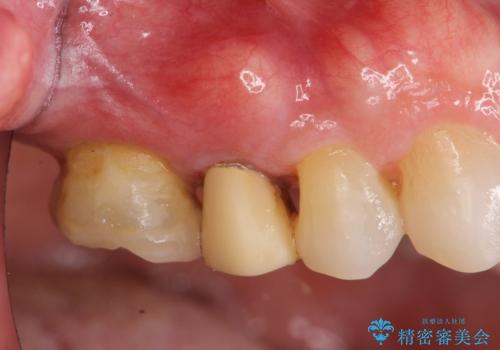

- かぶせてある歯が数日前からぐらぐらするので付け直してほしい、と希望され来院されました。

かぶせ(以下クラウン)を外してみたところ、神経のない支台となる歯が折れてしまい抜歯を余儀なくされる状況でした。